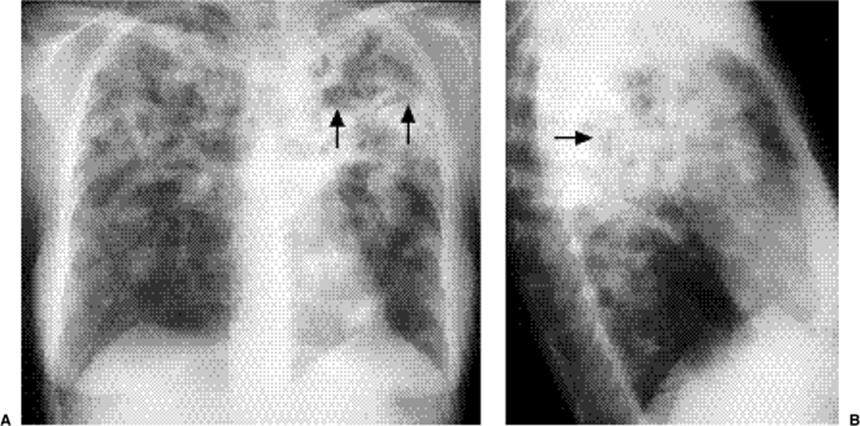

Figure 5.12 Pneumonia (P) enlarging the right upper lobe, suggesting the correct diagnosis of Klebsiella pneumonia. (A)Posteroanterior and (B) lateral chest radiographs: note bowing of major fissure (arrows). There is an associated pleural effusion (E).

Figure 5.13 Cavitary pneumonia. (A) Posteroanterior, and (B) Lateral chest radiographs: cavity with a gas-fluid level (arrows) in the superior segment of the right lower lobe.